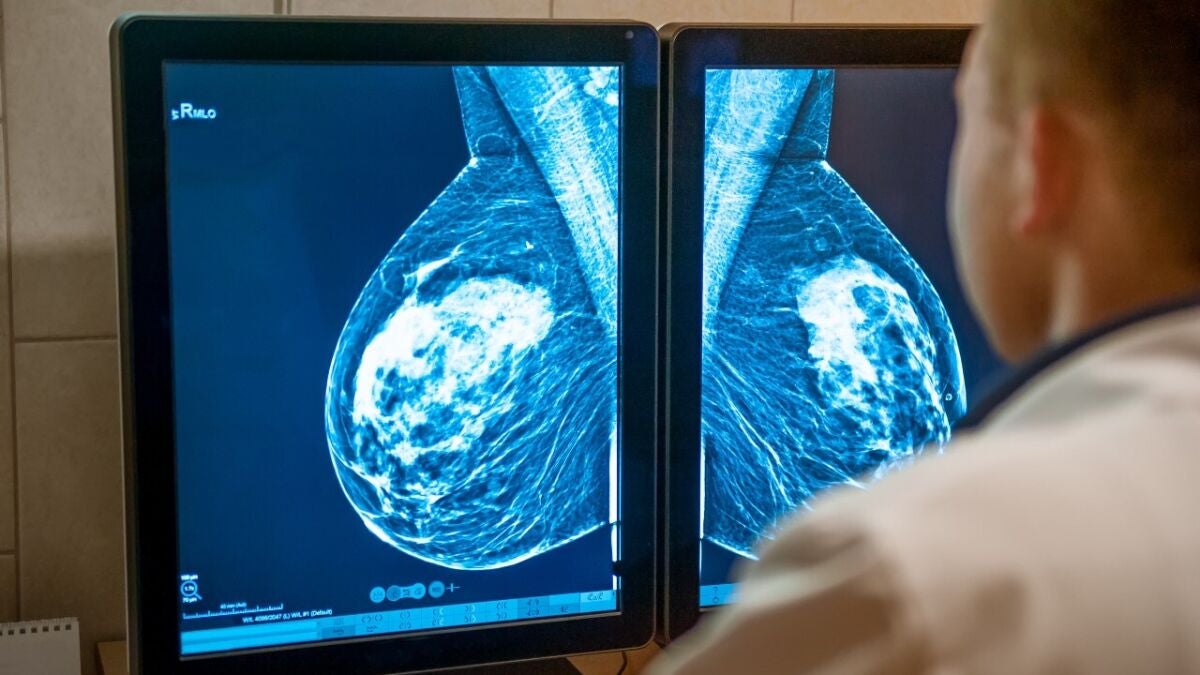

A favor, diagnósticos cada vez más rápidos y certeros, gracias a la IA. "Lo que antes se tardaba varias semanas en saber, ahora con este software de IA, tenemos el resultado en apenas treinta segundos"